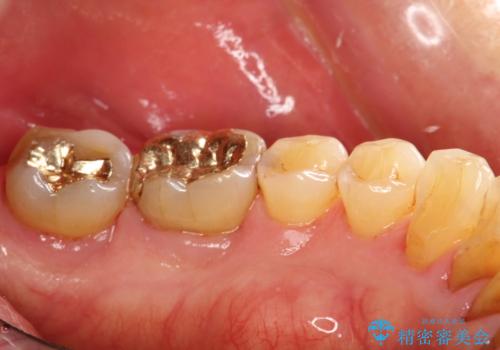

- 2カ月ごとにメンテナンスにいらしている方です。染め出しをしての歯磨きチェックとPMTC30分コースを行いました。

口腔内にはたくさんの細菌がいるため、ヌルヌルとしたプラーク(歯垢)が自然に歯の表面に付きます。

このプラーク(歯垢)にはたくさんの細菌が潜んでおり、虫歯や歯周病・口臭などの最大の原因です。そのため、毎日の歯磨きでプラーク(歯垢)をキレイに取り除くことが、健康な歯を保つためには欠かせません。